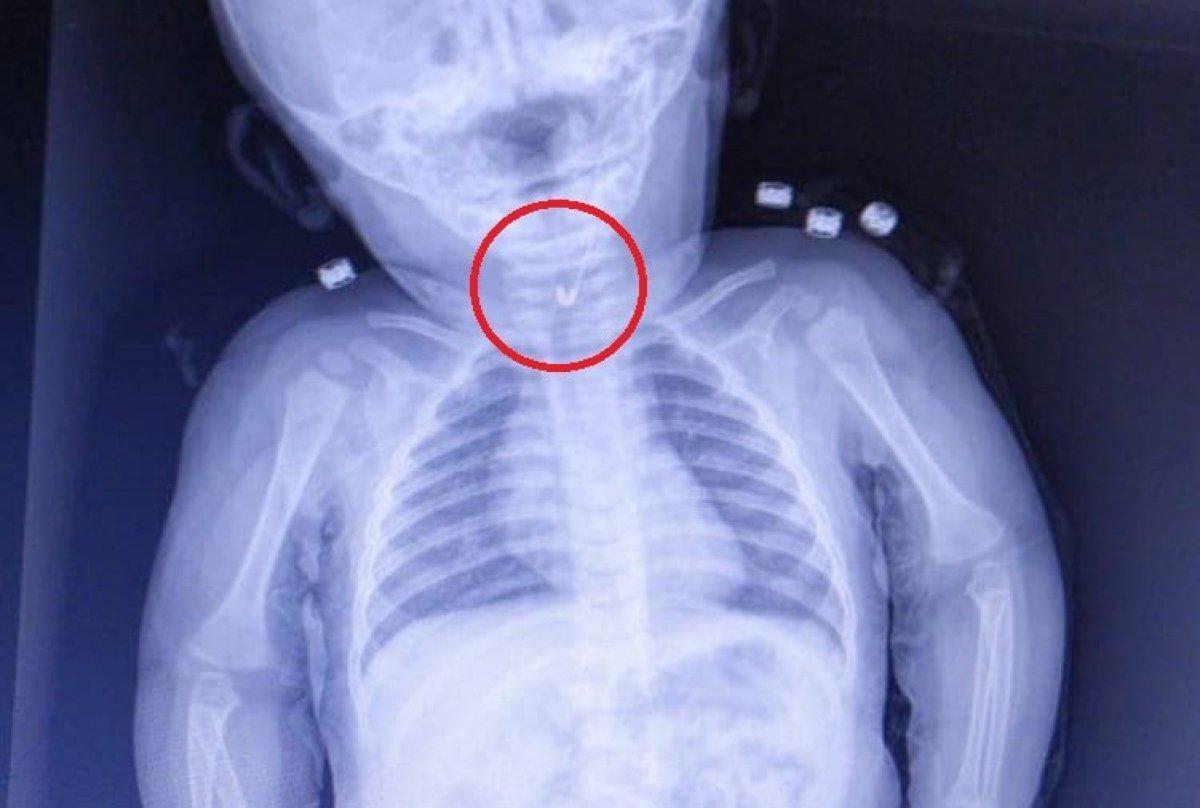

Bebeği muayene eden Gastroenterolojik Cerrahi Uzmanı Dr. İhsan Gündüz ve Anestezi Uzmanı Dr. İbrahim Çetin, yabancı cisim yutulmasından şüphe ederek röntgen istedi.

YEMEK BORUSUNDAN ÇENGELLİ İĞNE ÇIKTI

Çekilen röntgende, bebeğin çengelli iğne yuttuğu tespit edildi. Bebeğin yemek borusuna saplanan iğne, endoskopik yöntemle çıkarıldı. Hastane Başhekimi Aykut Demirkıran, bebeğin sağlık durumunun iyi olduğunu belirtti.